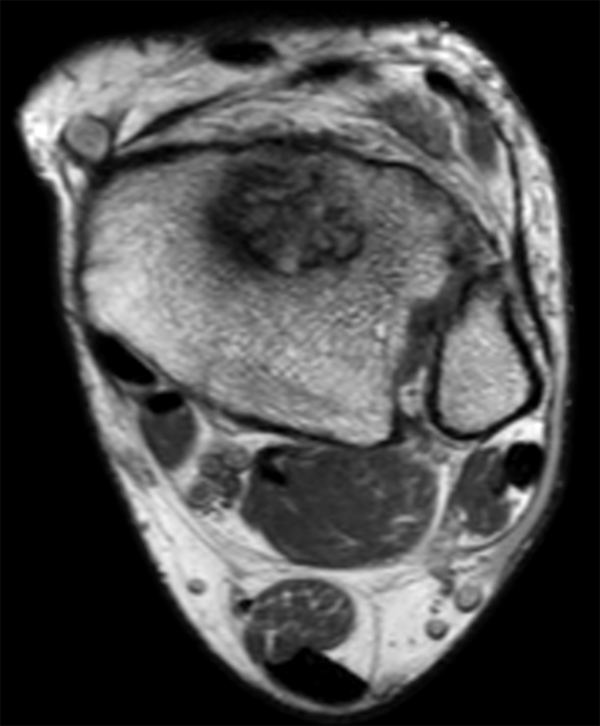

Axial T2w TSE